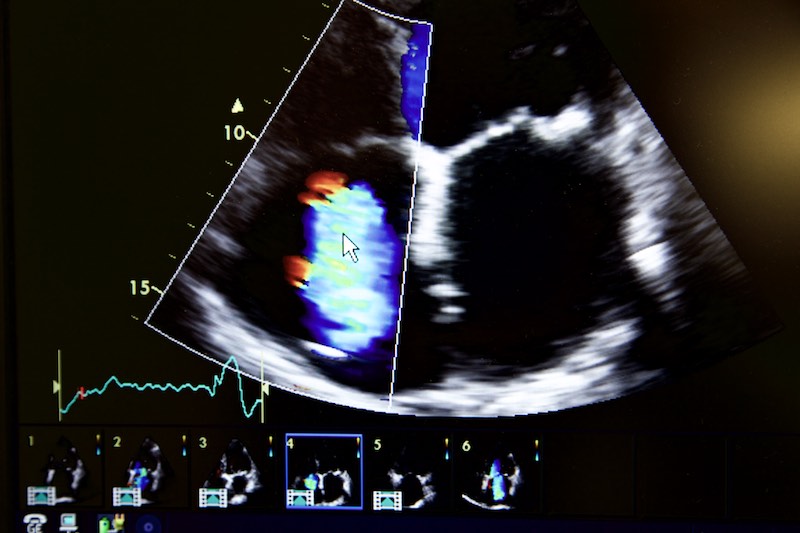

Echokardiographie (TTE)

Die Echokardiographie oder Herz - Ultraschalluntersuchung wird bei uns nach den neuesten technischen Standards durchgeführt. Die Untersuchung dient zur Beurteilung der Herzfunktion und der Größe der einzelnen Herzkammern sowie der Funktion der Herzklappen.